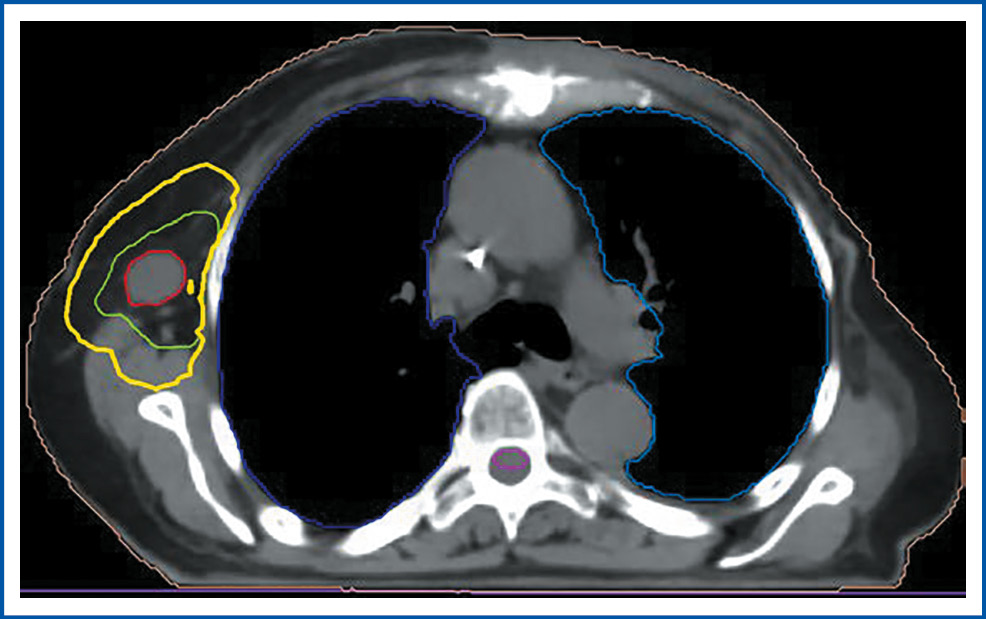

В отдел лучевой терапии МНИОИ им. П.А. Герцена – филиала ФГБУ «НМИЦ радиологии» с 14 по 20 июня 2022 г. по витальным показаниям проведен курс конформной дистанционной ЛТ на ускорителе электронов Elektra Infinity. В область gross tumor volume (GTV) вошли все определяемые опухолевые очаги по данным ПЭТ-КТ: узел передней грудной стенки в области грудины с мягкотканым компонентом, рукоятка и тело грудины, клетчатка переднего средостения, паратрахеальный лимфатический узел справа; конгломерат парааортальных лимфатических узлов на уровне дуги аорты, лимфатические узлы шеи, надподключичной области с обеих сторон, clinical tumor volume (СTV): GTV + 10 мм. Planned tumor volume (PTV) сформирована с отступом краниокаудально 12 мм, 10 мм в остальных направлениях от CTV. РОД – 6 Гр 5 раз в неделю, СОД – 30 Гр. Биологическая эквивалентная доза (EDQ2), рассчитываемая на основе LQ-модели, в данном случае составила 54 иГр при α/β=3.

На рис. 3 отражено дозное распределение в облучаемом объеме.

Рис. 3. Дозное распределение в объеме облучения (в процентах указана 95 и 80% изодозная кривая).

Fig. 3. Dose distribution in the irradiation volume (95% and 80% of the isodose curve are indicated in percentage).

Получено хорошее дозное покрытие:

- GTV – 100% доза покрывает 100% объема;

- CTV – 95% доза покрывает 95% объема;

- PTV – 95% доза покрывает 95% объема.

Толерантные дозы на критические органы не превышают допустимых по QUANTEC.